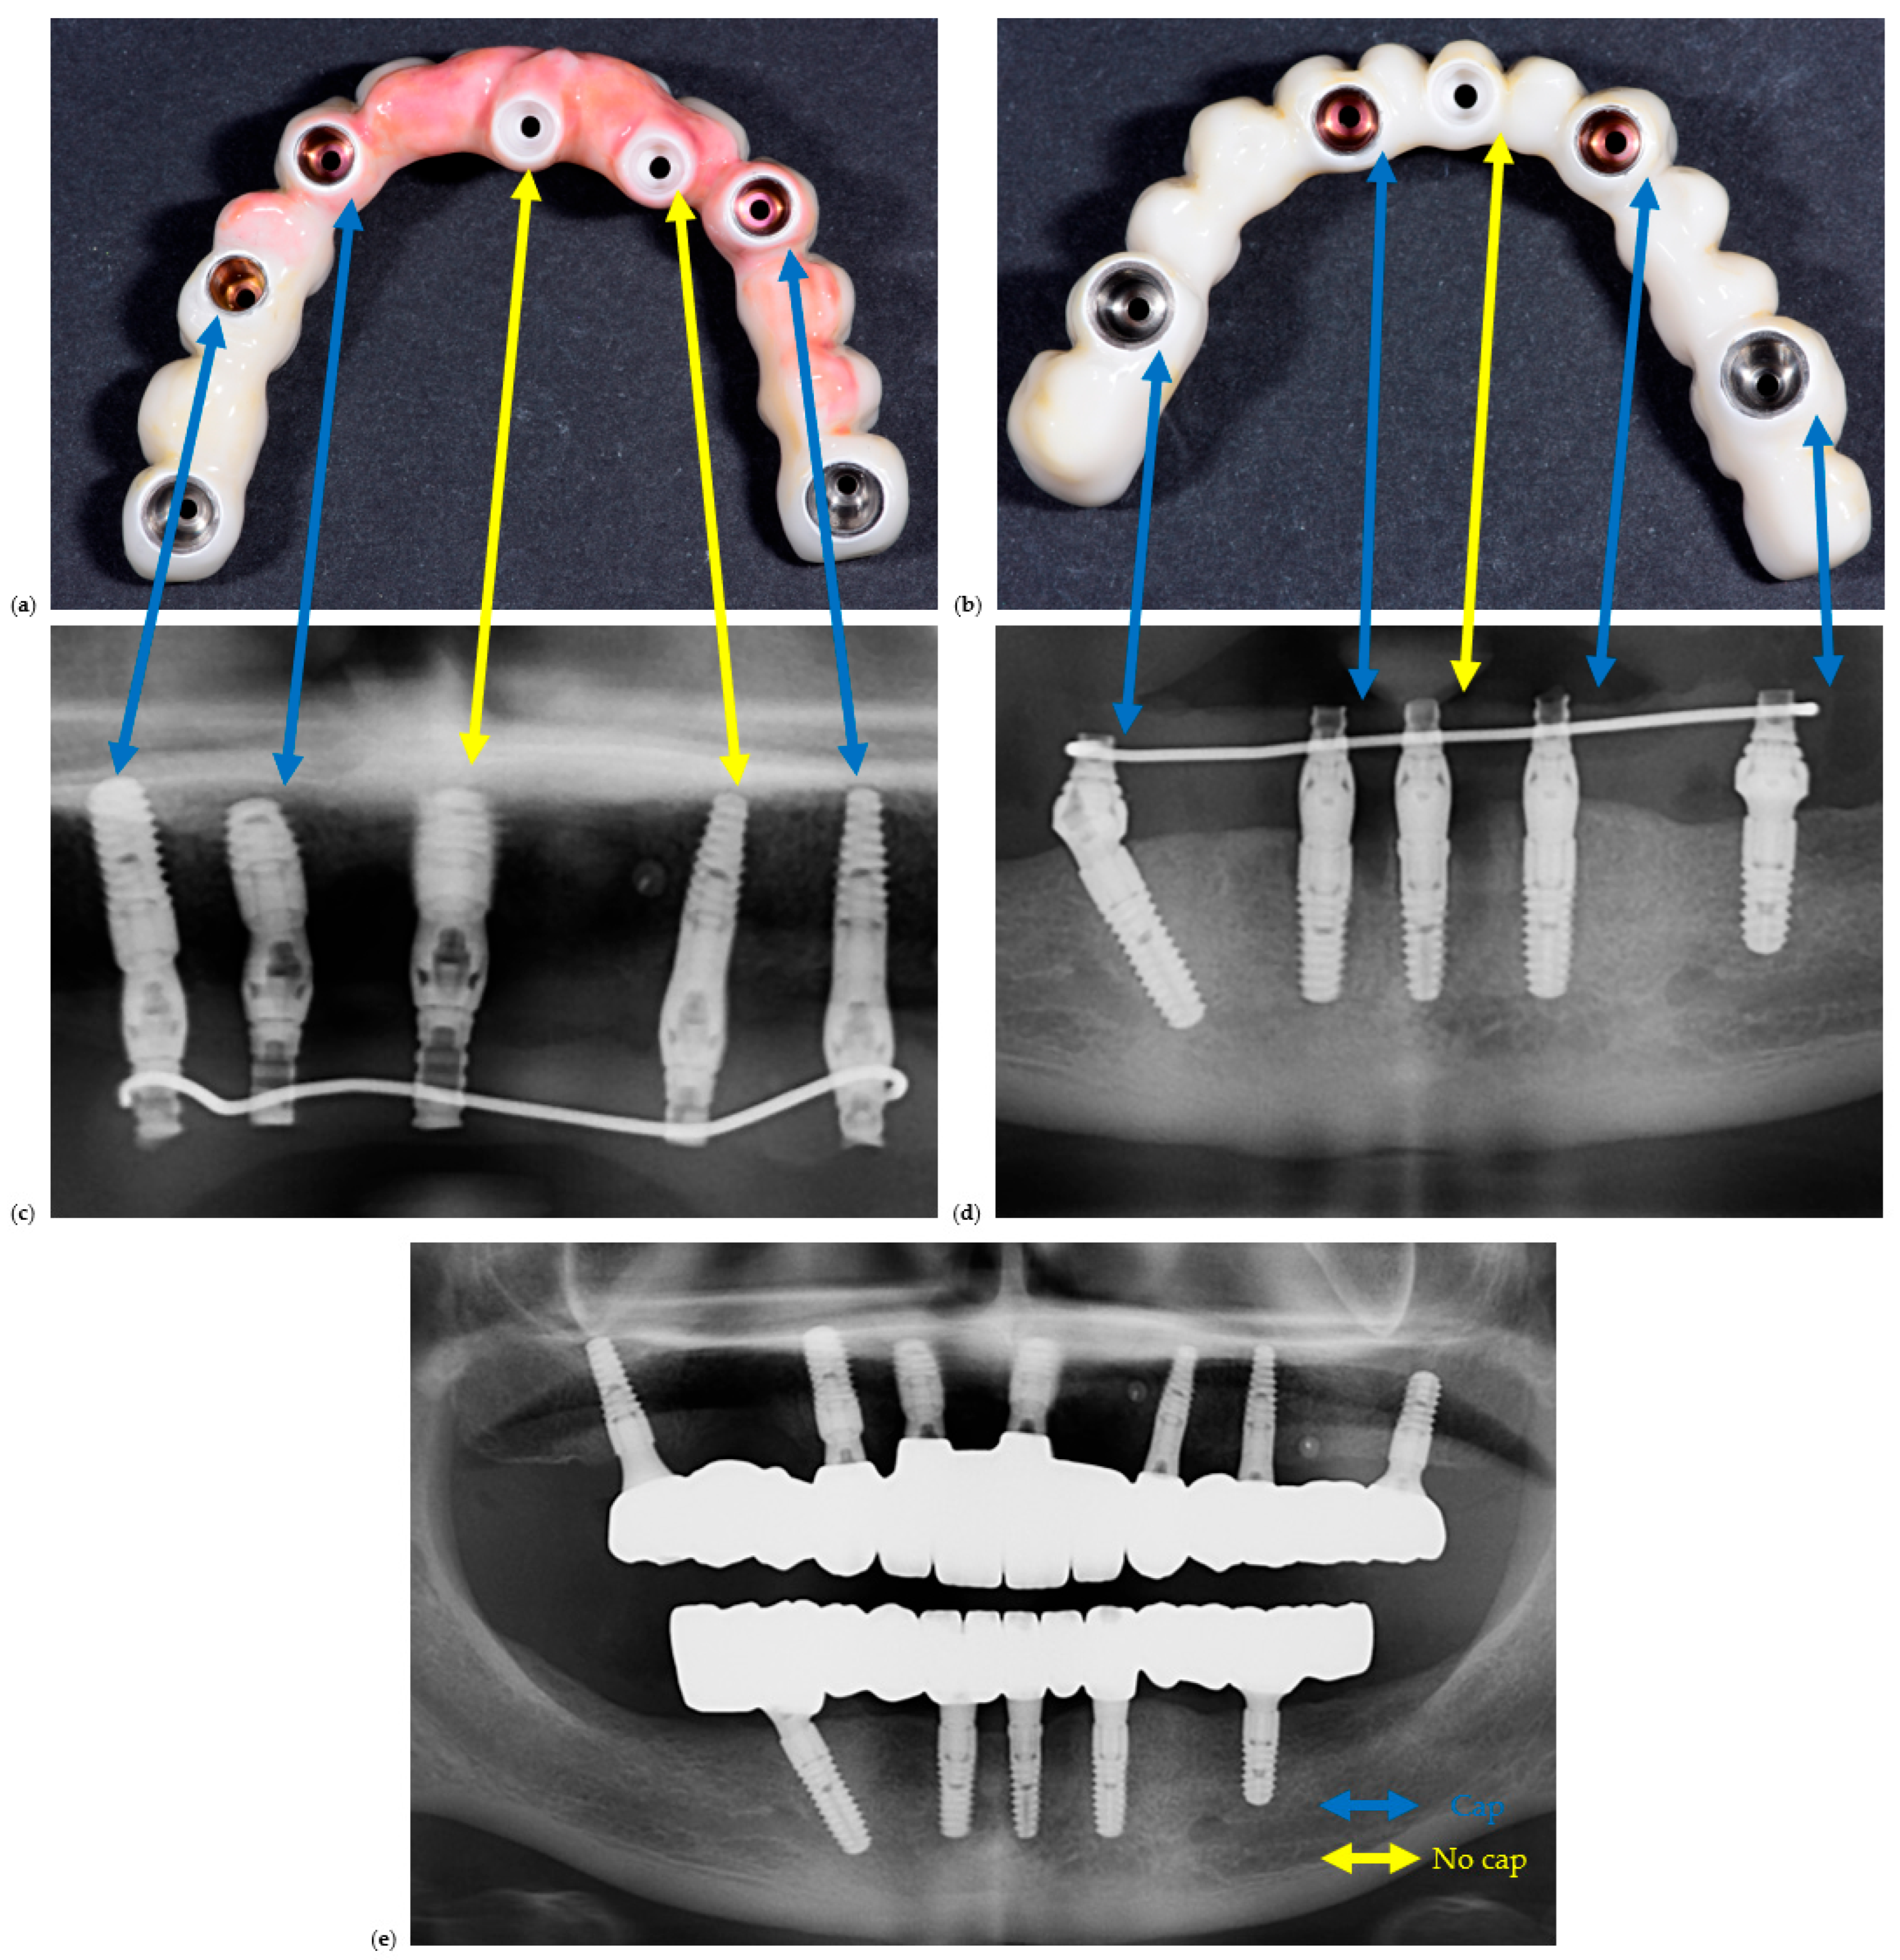

A representative example of restorations fabricated with and without prosthetic caps is illustrated in Figure 2 to demonstrate the restorative configurations compared in this study.

Clinical and radiographic comparison of screw-retained full-arch restorations fabricated with and without prosthetic caps. (a) Clinical photo of a maxillary full-arch screw-retained restoration, (b) clinical photo of a mandible full-arch screw-retained restoration, (c) section of an OPG corresponding to (a), (d) section of an OPG corresponding to (b). Blue lines are between implant sites with caps, while yellow lines are between implant sites with caps. (e) is the OPG of the final delivered restorations.